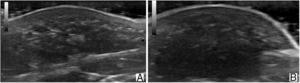

Ultrasound image (18MHz) of fibrolipomatous hamartoma. A, Longitudinal plane (A). B, Transversal plane (B). Note the thickening of the dermis and hypodermis at the expense of hypoechoic islands with fatty echogenicity intermingled between hyperechoic lines in the deep dermis, which extend to the subcutaneous cellular tissue.

DiscussionSkin imaging with high-frequency ultrasound is increasingly used in childhood dermatologic diseases. The differential diagnosis of tumors is one of its main applications. Unlike tumors, hamartomas appear as thickening of the dermis and/or subcutaneous cellular tissue and not as masses. The echogenicity of a hamartoma depends on the most abundant element. In the case of CFH, the reticular dermis thickens owing to the presence of islands of fatty tissue between collagen fibers that can extend to the hypodermis. Ultrasound reveals hypoechoic islands surrounded by hyperechoic bundles in the deep dermis and in the subcutaneous cellular tissue. The literature contains few references to ultrasound assessment of CFH. Cambiaghi et al.5 present a series of 3 cases and report on the usefulness of ultrasound in the differential diagnosis, although they do not describe or present their imaging findings. Grilo et al.6 describe CFH as a poorly defined, homogeneous, slightly hyperechoic lesion adjacent to the subcutaneous cellular tissue; however, their report does not show the ultrasound image. Our search of the literature revealed only 4 ultrasound images, and, despite differences in the descriptions, each of the 4 images shows findings similar to those we report.2,7–9 It seems reasonable to think that the more or less hypoechoic appearance of the lesion depends on the amount of adipose tissue in the hamartoma.